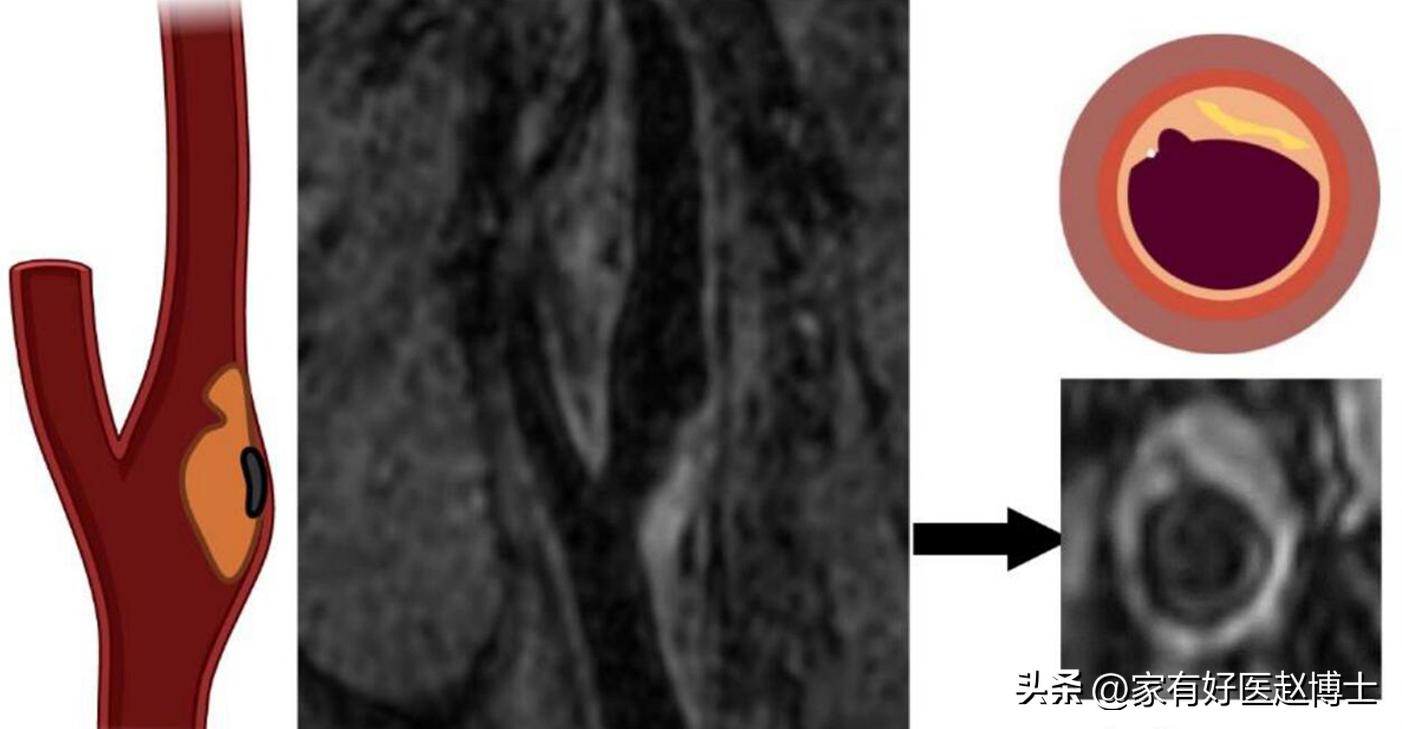

医学研究表明,当斑块在超声上表现出某些特定征象时,往往提示稳定性较差、容易发生破溃从而引起心血管事件,而这样的一些征象就被命名为“高危斑块特征”。

比较典型的“高危斑块特征”有以下这些:

第一,溃疡型斑块。 这主要是指斑块的“表面”不光滑、不平整,有类似“溃疡”的表现;

第二,无回声/低回声斑块。 这里所说的“无回声”或者“低回声”斑块,不仅包括以无回声或低回声为主的斑块;同时,也包括存在部分无回声或低回声区域的“混杂/混合回声”斑块。简单来说,只有内部回声均匀且以“等回声”或“强回声”为主的斑块,才属于相对比较稳定的斑块;而除此以外的“低回声”、“无回声”以及“混杂回声”斑块,则多属于相对不稳定的高危斑块;

第三,管腔旁暗区面积较大。 具体来说,有研究提出:如果超声报告提示颈动脉管腔旁的暗区(低回声)面积>10mm²,那么,后期发生脑卒中的风险会明显增加;

第四,斑块内有明显的新生血管;

第五,斑块内存在出血迹象;

第六,斑块表面有“微栓子”形成的迹象等等。

2022版《动脉粥样硬化斑块的筛查与临床管理专家共识》专门指出:假如动脉斑块存在2个或者更多的“高危特征”,那么,哪怕它并没有引起颈动脉的明显狭窄,也依然会认为具有“极高危”的心血管风险。

而另一方面,即便IMT没有超过2.5mm,但只要存在任何一条“高危特征”,那么,这种斑块也会被认为具有“高危”风险。

举例来说,一个IMT<2.5mm的颈动脉斑块,如果是一个以低回声为主的“软斑块”,那么,它至少属于“高危”这个风险级别。而假如除了低回声以外,这个斑块同时还属于溃疡型斑块,那么,它的风险级别就不止“高危”,而是“极高危”了。